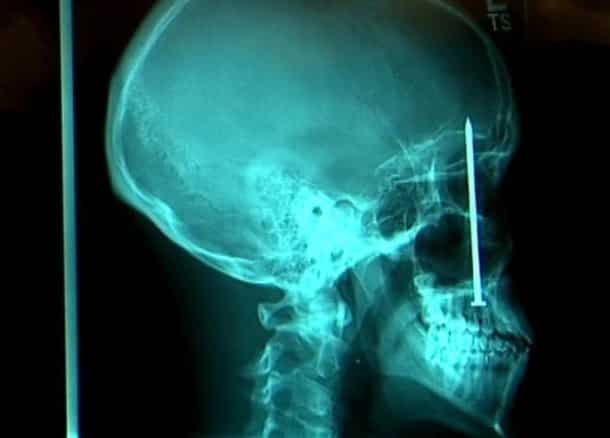

Accident, incident de pistolet à clous ou introductions douteuses de choses douteuses dans des parties douteuses de leur corps…voilà un petit aperçu de ce que voient les médecins au quotidien…

Certaines radiographies sont impressionnantes mais relèvent d’accidents…d’autres en revanche…